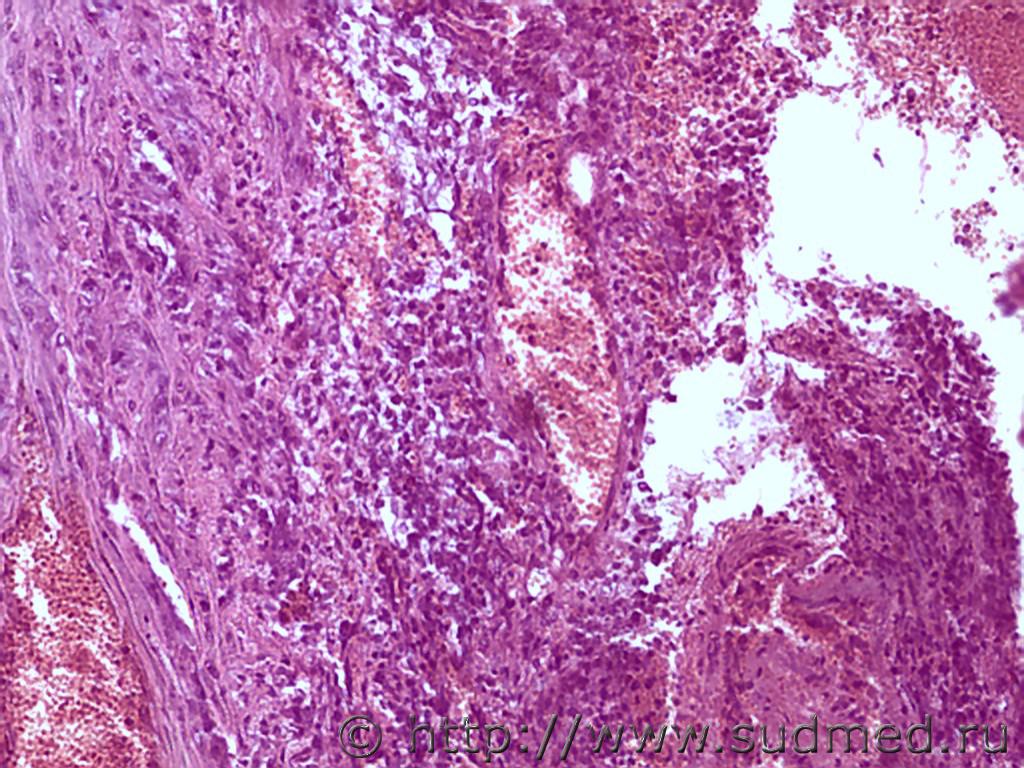

Уважаемые коллеги, подскажите, не похожа ли патология в аорте на синдром Такаясу? Опыта в подобных заболеваниях у меня нет, боюсь пропустить. На секции молодой парень 1995 г.р с тампонадой сердечной сорочки (645 мл), разрывом восходящей дуги аорты (макро танатолог видит в аорте атеросклетоз), сердце большое, 620 г, ЛЖ=2,2 см.

Хр.продуктивное воспаление + гигантоклеточный метаморфоз = неспецифический аортоартериит.

+деструкция и расслаивающее мезаортальное кровоизлияние, пристеночный тромбоз, париетальный эндокардит и не исключается миокардиты и субэндокардиальные инфаркты, септические эндокардиты ...

+ нужно искать пороки сердца, как коллеги отметили морфологию Марфана и Такаясу, пороки развития легочного ствола и коронарных артерии.

Но по микроморфологии аорты парень был не совсем здоровым т.к.продуктивный мезаортит с расслоением стенки аорты и разрывом стенки, кроме того огромная масса ни одного дня развития.